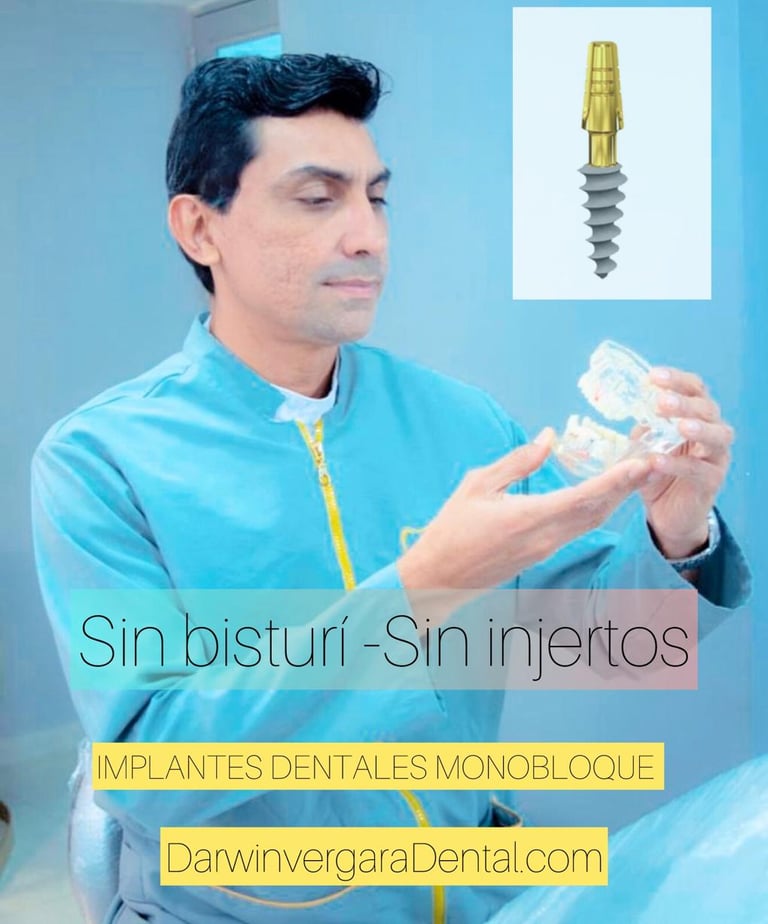

Implantes Monobloque

IMPLANTES DENTALES-SIN ABRIR ENCIA-SIN COLGAJOS-MINIMAMENTE INVASIVOS-DIENTES INMEDIATOS

Implantes Monobloque

Implantes dentales sin cirugía.

Sin abrir encía.

Sin puntos de sutura.

Ideal para personas con poco hueso o edad avanzada.

Dientes inmediatos / 24 horas .

Implantes dentales innovadores

Implantes monobloque sin cirugía y dientes inmediatos.

Innovación en Implantologia Dental